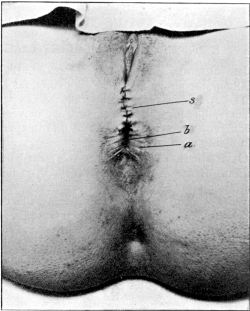

| 30. | Complete Laceration of the Perineum | 127 |

| 32. | Complete Laceration of the Perineum | 128 |

| 33. | Complete Laceration of the Perineum | 129 |

| 34. | Laceration of the Pelvic Floor | 132 |

| 35. | Repair of a Lacerated Perineum, with Non-union of the Sphincter Ani, before a Plastic Operation | 133 |

| 36. | Repair of a Laceration of the Perineum after a Plastic Operation | 133 |